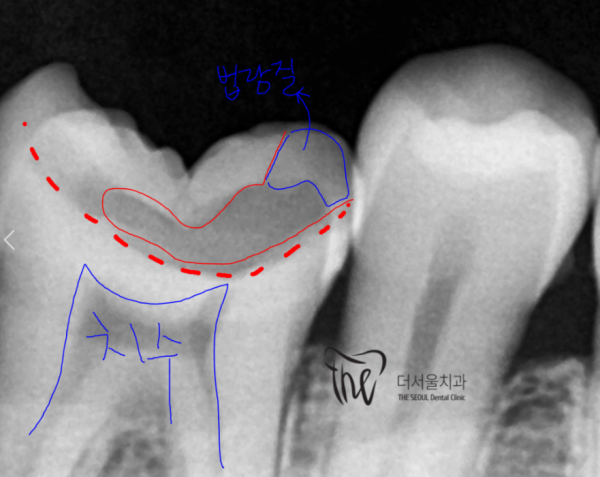

위의 사진을 보면, 법랑질을 넘어 상아질까지 넓게 충치가 있어

치수 가까이 충치가 진행된 상황입니다. 때문에 신경치료 필요한 상황입니다.

If you look at the picture above, there's a wide cavity beyond enamel to ivory.

The cavity has progressed close to the size. Therefore, neurosurgery is necessary.

신경치료를 진행하는 상태의 엑스레이 사진입니다.

This is an X-ray of the state of neurotherapy.